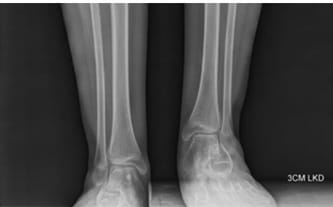

Po zabiegu lewa noga syna skróciła się o 3 cm i została wykręcona do wewnątrz, powodując nieustanne cierpienie i rany. Po pewnym czasie wykonano tomografię, która potwierdziła, że konieczna jest kolejna operacja. Nie chciałam, by Filip znów przechodził podobny zabieg, dlatego postanowiłam poszukać pomocy w innych miejscach.

Nadzieja pojawiła się w klinice Paley European Institute w Warszawie. Specjaliści przygotowali plan naprawczy – usunięcie metalowych implantów, korekcyjną osteotomię, wyrównanie długości kończyn i intensywną rehabilitację. Niestety, refundacja leczenia nie jest możliwa, a koszt zabiegu jest dla mnie nieosiągalny…